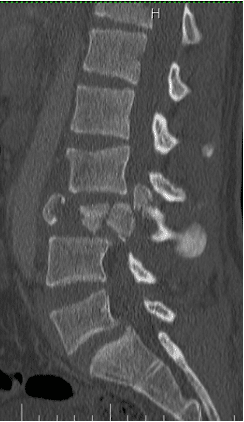

Un chico de 18 años se cayó desde tres pisos. Pérdida casi total de todas las funciones neurológicas por debajo del nivel de lesión con afectación casi total del intestino y la vejiga

El paciente fue operado y el conducto espinal limpiado de todos los fragmentos óseos. La columna vertebral se fijó de lado y la parte trasera para eliminar la inestabilidad.